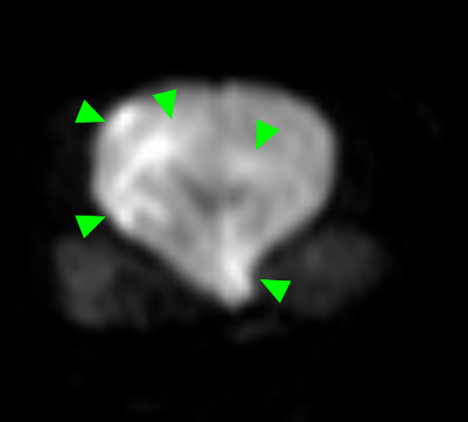

本症例のMRI検査所見:

・前頭葉白質領域(右>左)および右側大脳白質領域(側頭葉・後頭葉)にT2強調画像/FLAIR画像で高信号を示し、一部造影増強を示すびまん性の所見を認める。この所見は、DWI画像で高信号を示し、ADC-mapで大半は等~低信号を示す。